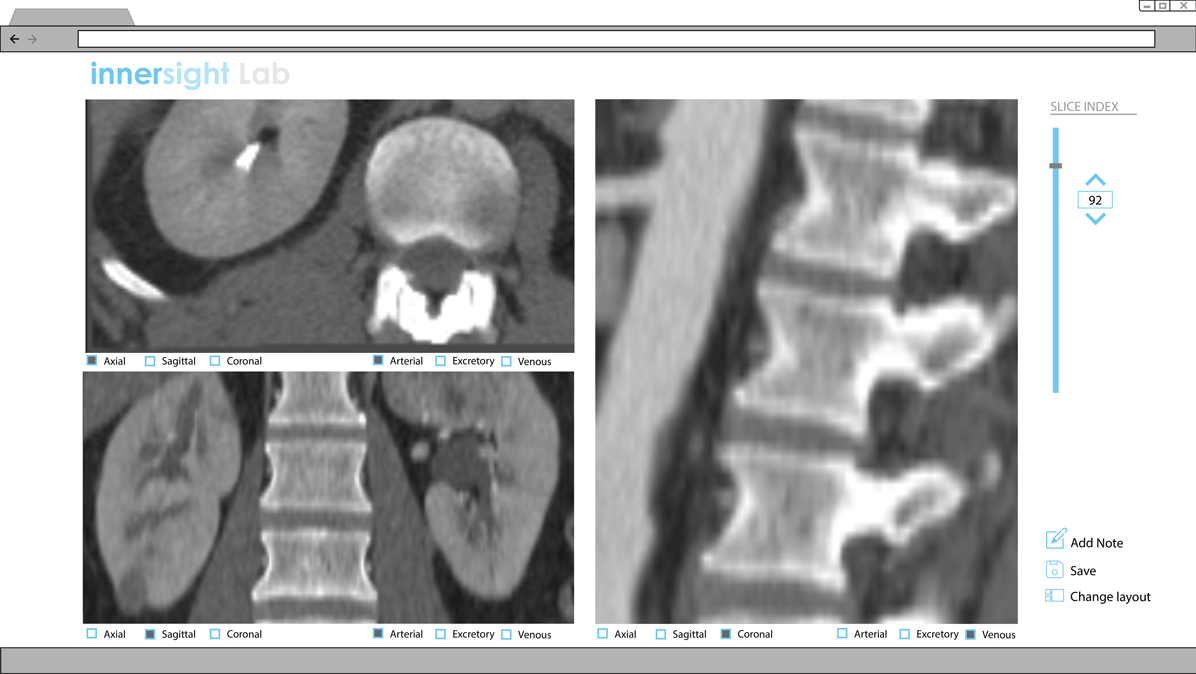

Proposed Interface for CT scans

The logic of presenting functionalities to users without having to open various buttons is applied to the interface for CT scans. Presently, a dropdown menu is presented at the top right corner to toggle between the various phases and views.

Proposal for Multi-View layout

Version 1

Control what's shown by clicking and unclicking boxes.

Clicking the 'Change layout' button opens up this menu.

Version 2

Control what's shown by the dropdown menu. Toggle between various view configurations by the icons.